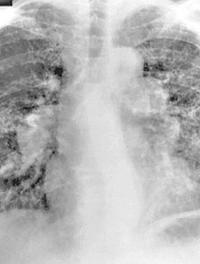

La sarcoïdose est une maladie multi-organique de cause inconnue caractérisée par une inflammation granulomateuse non nécrosante, touchant [...]